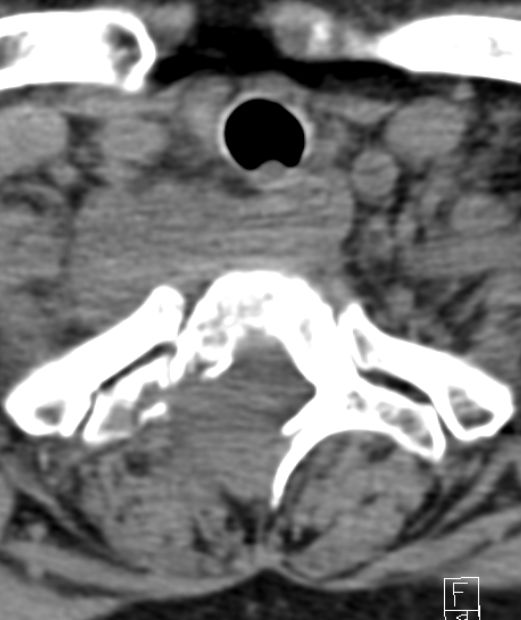

64-jähriger Mann mit einer Osteolyse C6/C7.![]() | |||